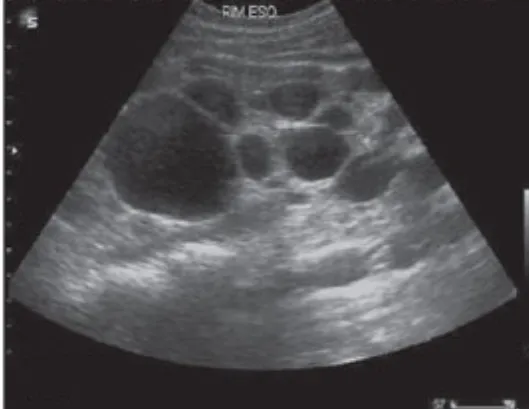

Diálise Peritoneal na Doença Renal Policística: existe algum motivo para não indicar?

A DRPAD não é contraindicação à DP — e, na prática, muitos pacientes têm resultados comparáveis à hemodiálise. O “porém” está na mecânica: rins/hepatomegalia podem reduzir tolerância a volumes, aumentar risco de hérnias e extravasamentos, e piorar desconforto respiratório. Com técnica adequada (cateter presternal ou lateral, volumes menores, cicladora noturna e decúbito supino), a maioria das barreiras é contornável. Neste post, revisamos quando a DP é ótima, quando exigir cautela e como ajustar a prescrição para segurança e qualidade de vida.